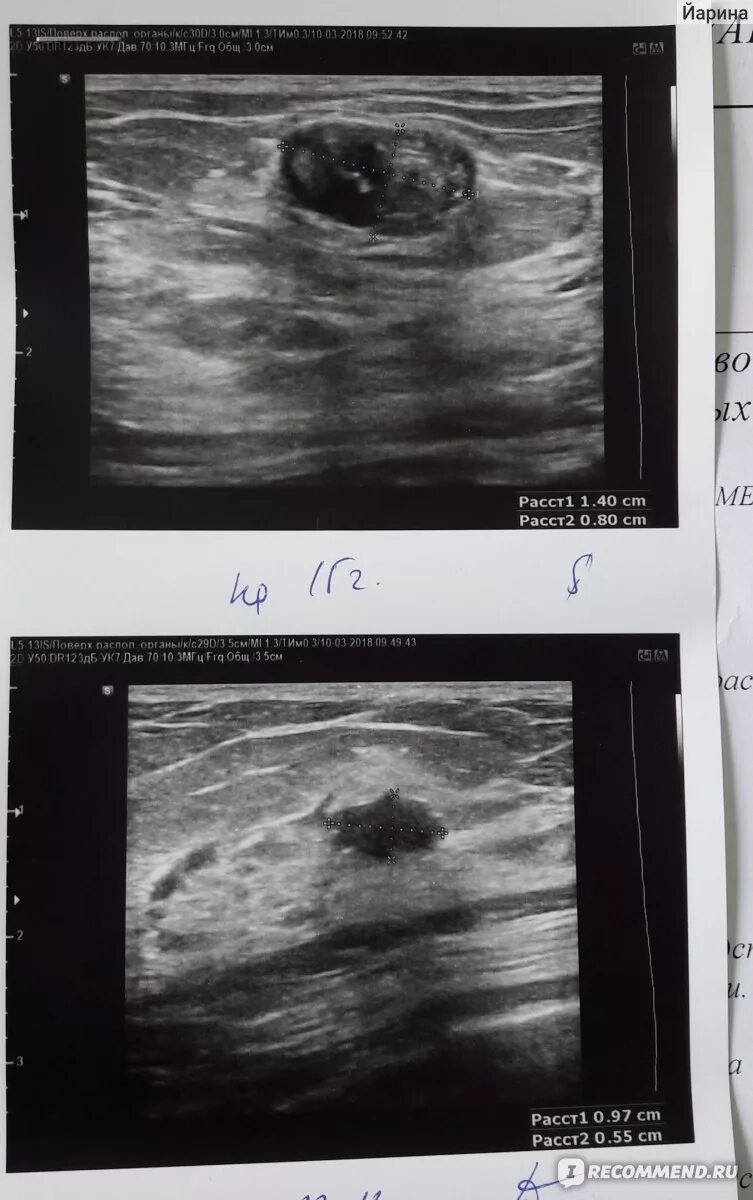

Удалить фиброаденому молочной железы отзывы